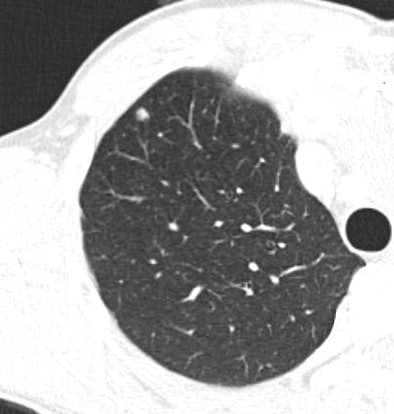

|

| Contrast enhanced spiral CT study in a 49-year-old woman with a history of colon cancer. A 7-mm soft tissue lung lesion was missed at clinical interpretation but detected by CAD. The location of the lesion in the immediate vicinity of lung vessels of similar size may have prevented its detection at the initial readout. A yellow line indicates the anatomical level of the displayed section within the volume data set in a coronal maximum intensity projection of the pulmonary vascular tree (left upper image panel). 3D volume rendering (left lower image panel) of the lesion highlighted in green displays the spatial relationship of the lesion relative to surrounding vascular structures and enables better differentiation of focal lung lesions and vessels than individual axial sections. Image courtesy of Dr. Joseph Schoepf. |